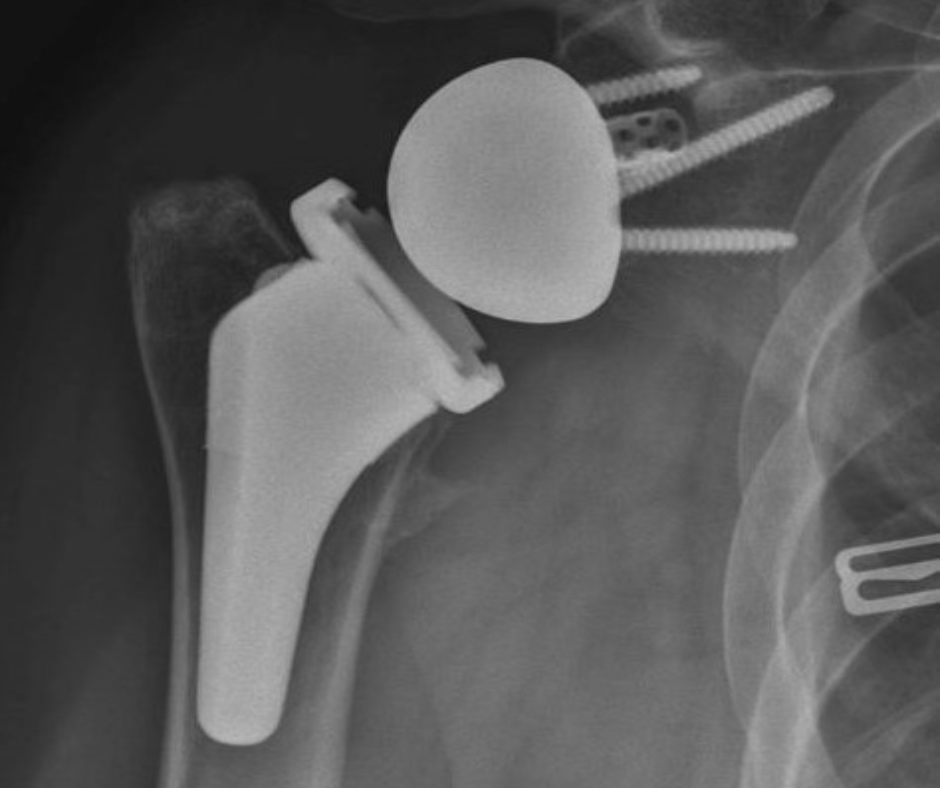

Reverse Total Shoulder Replacement

In patients who have a history of a rotator cuff injury, reverse total shoulder replacement surgery is performed. During this procedure, your natural anatomy is reversed, which changes the mechanics of your shoulder and allows for better overall function.